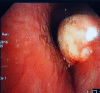

Isolated pulmonary mucormycosis